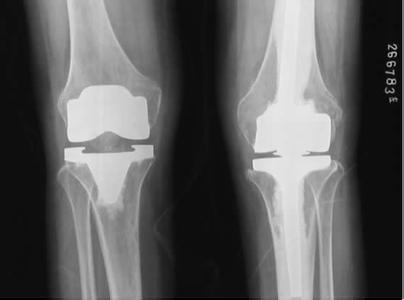

(圖:膝關節(jié)風濕性關節(jié)炎的CT檢查影像圖)

6、X線檢查。于X線平片上可以發(fā)現(xiàn)以下改變:(1)、軟組織腫脹:顯示關節(jié)囊陰影增大;(2)、關節(jié)間隙變窄:由于軟骨受累及缺損所致;(3)、關節(jié)周圍骨質(zhì)疏松:顯示關節(jié)周圍骨質(zhì)中的骨小梁減少、萎縮及變細。

7、其他影像學檢查。CT及MRI成像技術可酌情選用,尤其是對早期病例。